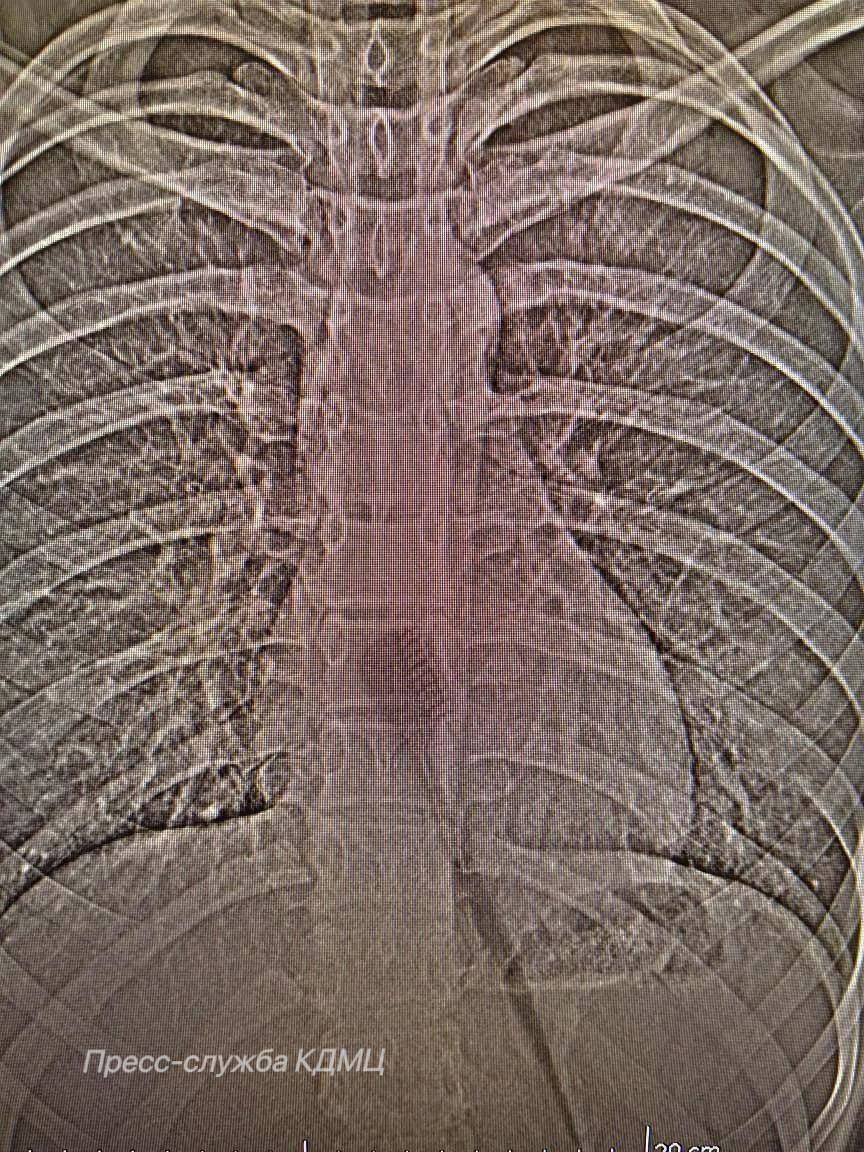

В Челнах 13-летняя девочка проглотила зубную щетку

Врачи смогли достать инородное тело без разрезов

В КДМЦ Набережных Челнов поступила 13-летняя пациентка, которая случайно проглотила зубную щетку длиной 19 см. Как сообщает горздрав, щетка находилась в желудке и частично в пищеводе, создавая риск повреждения этих органов.

Врач-хирург КДМЦ Дамир Хузин говорит, что механизм проглатывания в данном случае является стечением обстоятельств.

«Предположительно, произошла неожиданная реакция, возможно, резкий вдох или смех во время чистки зубов. Это могло спровоцировать непроизвольное сокращение мышц глотки, которое подтолкнуло щетку дальше по пищеводу. Так как анатомически пищевод имеет определенную эластичность, щетка, несмотря на свои размеры, смогла продвинуться вплоть до желудка», - объясняет врач.

Девочке провели эндоскопическую операцию – малоинвазивный метод, позволяющий извлечь инородное тело без полостного вмешательства. Это позволило аккуратно удалить предмет через естественные пути, минимизируя риск осложнений и ускоряя процесс восстановления пациентки.

Подросток прошла период реабилитации, была выписана из КДМЦ и вернулась к обычной жизни.

Случаи проглатывания инородных тел детьми – явление частое, но проглатывание предмета такого размера, конечно, редкость.